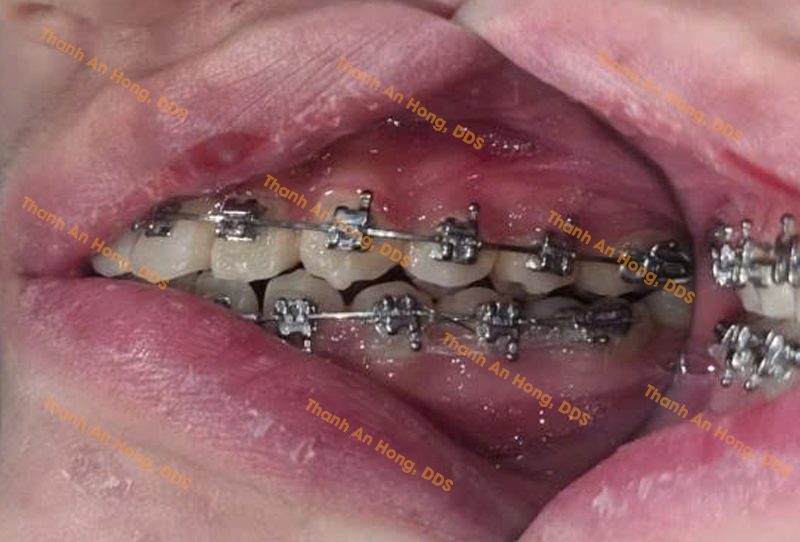

HÌNH ẢNH THỰC TẾ

Chỉnh mắc cài giảm hô